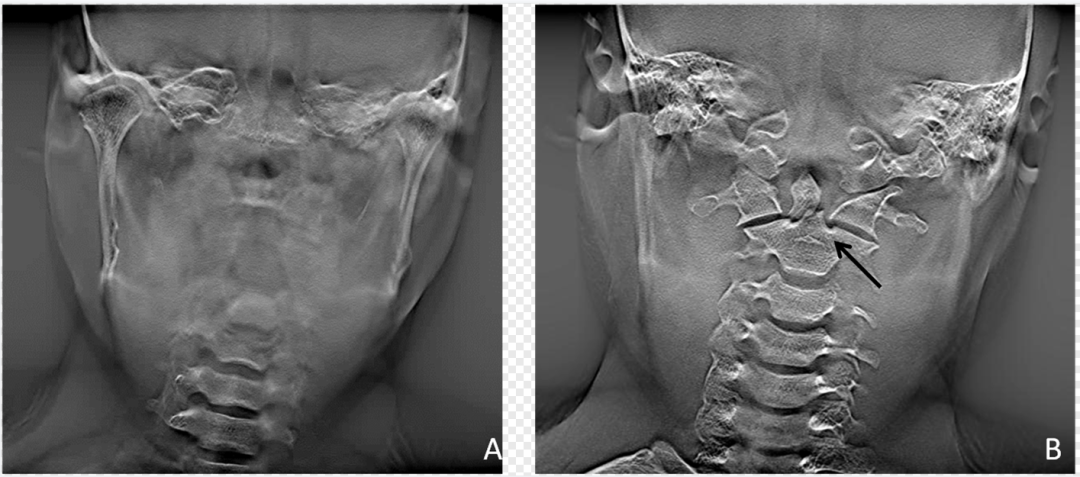

数字断层融合成像

在预设的融合体层曝光程序控制下,X线管组件完成多角度多次脉冲式曝光,结合位移叠加算法等数字化重建方法,创建检查区域内不同体层深度的聚焦层面图像。其中每幅图像的起始高度、层厚、层间距可以人为进行调整。DTS弥补了DR三维结构投影重叠的不足,空间分辨率高,相对于CT辐射剂量低。可清晰地显示骨折线,提高对隐匿性骨折的检出率和准确率(图1、图2)。

dr数字怎么用数字化X线摄影术(DR)_https://www.jmylbn.com_新闻资讯_第4张

图2  齿状突骨折常规DR与DTS

A.常规DR齿状突及周围组织显示较模糊;B.DTS显示清晰的齿状突骨折线(黑箭)